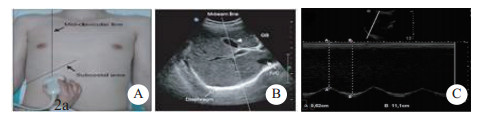

患者取仰卧位,暴露胸部及上腹部,在呼吸平稳后,利用超声凸阵探头(Sonosite M-Turbo 2~5 MHz),在双侧锁骨中线肋弓下,取样线尽可能与膈肌影像垂直,夹角最大不超过20°。应用M超模式记录膈肌与体表探头的距离。SBT 30 min后,测吸气相与呼气相的膈肌移动距离之差,分别测双侧膈肌移动度的数值,取平均值,称为膈肌移动度(即为DD),并记录,见图 1~2。

| A:膈肌检查部位于双侧锁骨中线肋弓下;B:获取的右侧膈肌超声图片(A、B图片来源:Ferrari G, De Filippi G, Elia F, Apra F, et al.Diaphragm ultrasound as a new index of discontinuation frommechanical ventilation. Crit Ultrasound J.2014 Jun 7;6(1):8)。C:表示M超模式下膈肌在吸气相与呼气相的运动幅度,虚线A代表呼气相膈肌距离探头的距离,虚线B代表吸气相膈肌距离探头的距离,线B的长度减去线A的即为膈肌移动度,即DD 图 2 膈肌超声检查及数据收集方法 |